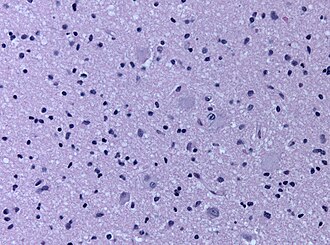

Cortical tubers are malformative lesions in the CNS observed in tuberous sclerosis complex (abbreviated TSC), an autosomal dominant syndrome.

- Cortical tubers are malformative, epilepsy-associated.[1]

- Seen in 80-90% of the TSC cases.

- Gyrus is usu. thickened, raised, and occasionally dimpled.

- Giant cells, dysmorphic neurons, gliosis, calcifications.

- Prominent cell loss in all cortical layers.[2]

- Normal cortical lamination is lost in the lesion.